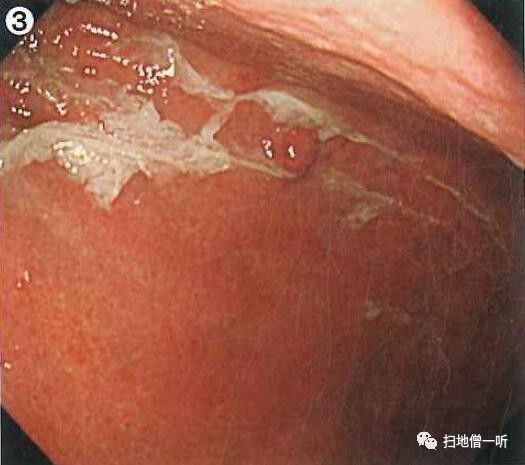

A:胃癌在图3及图6。HP现症感染胃癌。

背景粘膜为O-3型萎缩、肠上皮化生、弥漫性发红。胃体下部前壁可见小片粘膜发红,伴毛细血管扩张。毛细血管扩张常常提示癌性病变,需进行详细观察。正面观察时凸凹感不强。

切线位观察明确其为红色凹陷性病变。

NBI非放大模式下观察可见褐色凹陷区域。

靛胭脂染色后观察可见凹陷区域内胃小区不鲜明化,边界清晰。

抽气后切线位观察凹陷更加明显。

最终诊断:胃体下部前壁,O-IIc,10mm,tub1,T1a(M),UL(-)

小结:发现病变后需要通过改变距离,空气量,角度等进一步详尽观察

扩张的毛细血管伴凹陷考虑癌性病变。